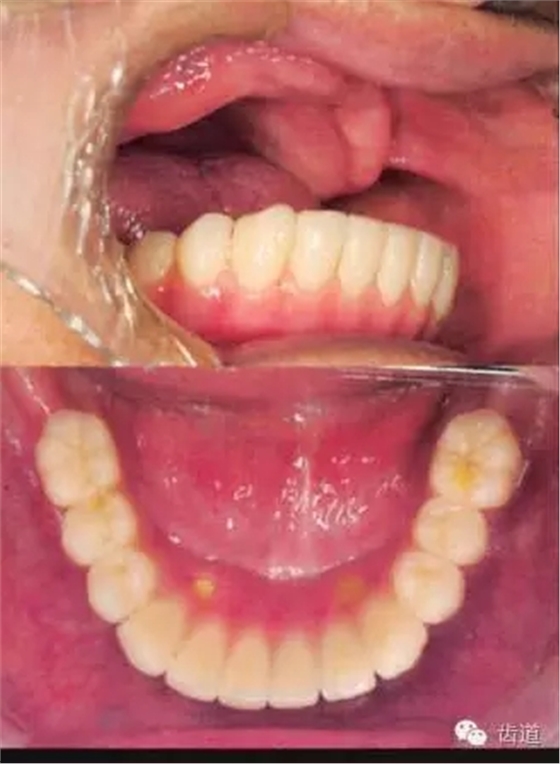

患者男性,81歲,一年前在其他醫(yī)院完成下頜All on Four的種植修復(fù)

因?yàn)樯项M義齒不適疼痛,要求修復(fù)

患者為重度Class III 類,雙尖牙以前的牙槽嵴嚴(yán)重吸收,前牙區(qū)牙齦松軟

患者就診時(shí),義齒組織面有很多的粘著劑